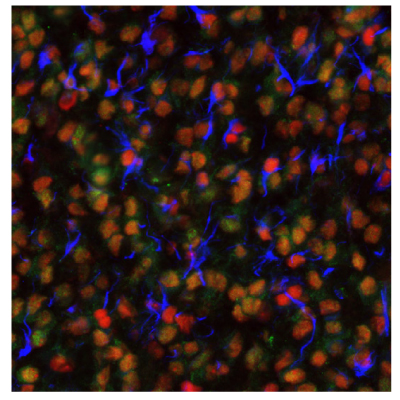

Figure 5 shows the high METTL21B expression in glioblastoma tumor cells as well as an increased number of activated microglial cells (HLA-DRA) compared to controls.

Figure 5A.Multiplexed IHC-IF staining of human normal cortex samples using Anti-HLA-DRA monoclonal (cytoplasmic, in green) and Anti-METTL21B polyclonal (nuclear, in red) antibodies. Nuclei are counterstained with DAPI (in blue). White arrow indicates activated microglia (HLA-DRA positive staining).

Figure 5B.Multiplexed IHC-IF staining of glioblastoma samples using Anti-HLA-DRA monoclonal (cytoplasmic, in green) and Anti-METTL21B polyclonal (nuclear, in red) antibodies. Nuclei are counterstained with DAPI (in blue). White arrows indicate activated microglia (HLA-DRA positive staining).